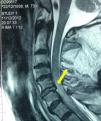

Caso 1Mujer caucásica de 44 años, sin antecedentes, que sufrió una caída y fue inmovilizada con collarín cervical semirrígido. En la exploración se comprobó una tetraparesia, sin otras lesiones aparentes. La tomografía computarizada (TC) de columna cervical evidenció una luxación de C5 sobre C6 (fig. 1). Se decidió fijación quirúrgica, por lo que explicamos y obtuvimos el consentimiento de la paciente para la técnica anestésica. A las 3 h del ingreso, en quirófano, tras monitorización básica, iniciamos perfusión de remifentanilo a 0,05μg· kg-1· min-1. Mantuvimos el collarín cervical e iniciamos oxigenoterapia a través de gafas nasales con capnografía. Administramos anestesia tópica con aerosol de lidocaína al 10% en la cavidad oral y la faringe, animando a la paciente a realizar gárgaras con la solución y aspirándola intermitentemente con una sonda flexible. A los 15 min confirmamos la anestesia de la zona introduciendo de forma progresiva una cánula oral específica para intubación con fibrobroncoscopio. A través de la cánula introdujimos un fibrobroncoscopio flexible, con un tubo orotraqueal (TOT) anillado de 7,5mm de diámetro interno previamente insertado. Una vez visualizada la glotis, administramos 3ml de lidocaína al 2% a través de un catéter flexible uniperforado introducido en el canal de trabajo del fibrobroncoscopio. A continuación, avanzamos el catéter a la tráquea y administramos otros 3ml de lidocaína. La paciente presentó una mínima tos refleja autolimitada e introdujimos el fibroscopio hasta objetivar la carina. Posteriormente, progresamos el TOT rotándolo 90° coincidiendo con una inspiración espontánea profunda de la paciente. La maniobra se realizó sin dificultad. Tras comprobar la posición del TOT con capnografía, realizamos una nueva exploración neurológica que descartó un agravamiento de la sintomatología e indujimos anestesia con propofol y rocuronio. Se llevó a cabo una artrodesis anterior sin incidencias y la paciente se recuperó sin secuelas.